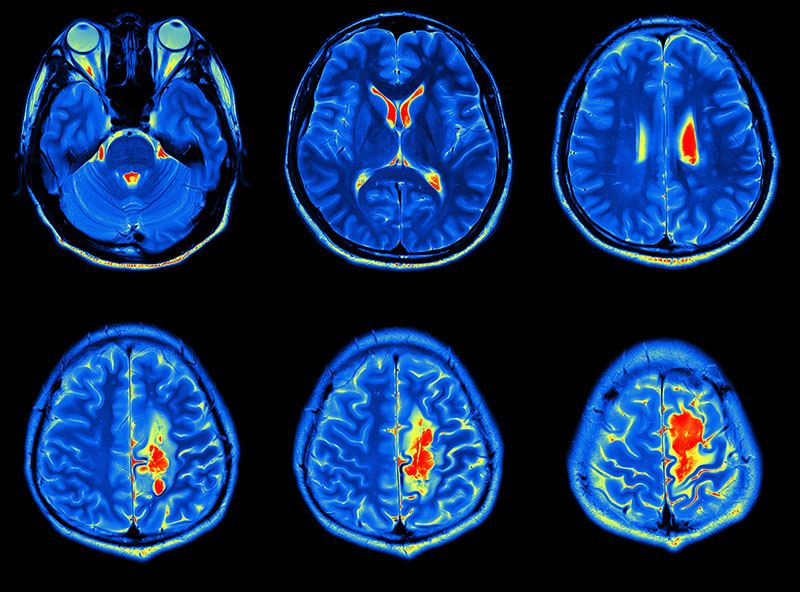

Beyin tümörü uyku hali. Yetişkinlerde ikincil beyin tümörleri birincil beyin tümörlerinden çok daha yaygındır. Ancak şikayetler çok daha çeşitlilik gösterebilir. 1925 yılından beri bilinen bu beyincik tümörü çok ayrı hücresel ve klinik özellikeri olan ve oldukça habis karekterli bir beyincik tümör tipidir beyinciğin çocuklarda en sık tümörü olup tüm primer beyin tümörlerininin 4 10 teşkil ederler. Patoloji alındı ondada tam teşhis konulmadı.

Gün içinde halsizlik ve sürekli uyku hali sabahları ise baş ağrısı ve ağız kuruluğu ile uyanmalar tipiktir. Uyku tüm tümörlerin ortak belirtisi değildir fakat bazılarında görülür. Beyin tümörü hastalarının son günleri nasıl anlaşılır. şimdi radyoterapi ve kemoterapi alıyor.

Uykuyu kontrol eden sinirler beyin sisteminde yer aldığı için sürekli uyku problemini çözmek için nöroloji bölümüne gitmeniz gereklidir. İkincil beyin tümörleri en sık kanser öyküsü olan kişilerde görülür. Denge kaybı uyku hali gözde görme sorunları duyma sorunları el ya da ayaklarda his sorunları ruhsal değişiklikler halüsinasyonlar görebilir yemek yeme sorunları yutkunma sorunları yemek yeme sorunları halsizlik trombosit düşüklüğü lökosit. Sadece uyku hali be yorgunluğu vardı.

Sonrasında bulantı kusma şuur dalgalanmaları uyku hali baş dönmesi ve nöbet geçirme vücudun farklı bölgelerinde kuvvetsizlikler iştahsızlık unutkanlık gelmektedir. Bunların en başında yeterince uyumamaktır. Ancak çocukluk yaşı tümörlerin 15 20 sini teşkil etmektedir. Beyin tümörü uyku yapar mı.

Nöbet geçirmesi şimdiye kadar olmadı. Uyku apnesi bulunanların kalp damar hastalıklarına ve beyin damar hastalıklarına inme gibi yakalanma riski daha yüksektir. Ancak baş ağrısı bazen beyin tümörü beyin kanaması ve anevrizma gibi yaşamı tehdit eden. Ancak nadir durumlarda metastatik beyin tümörü vücudunuzun başka yerlerinde başlayan kanserin ilk belirtisi olabilir.